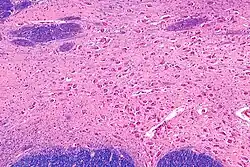

Jądro podstawne Meynerta (ang. basal nucleus of Meynert, NBM) – grupa komórek nerwowych istoty bezimiennej kresomózgowia, bocznie od guza popielatego, wysyłająca liczne projekcje do kory nowej. Stanowi część układu cholinergicznego mózgowia. Degeneracja jądra Meynerta obserwowana jest w przebiegu choroby Parkinsona, choroby Alzheimera i w otępieniu z ciałami Lewy’ego. Nazwa tej struktury anatomicznej upamiętnia Theodora Meynerta.